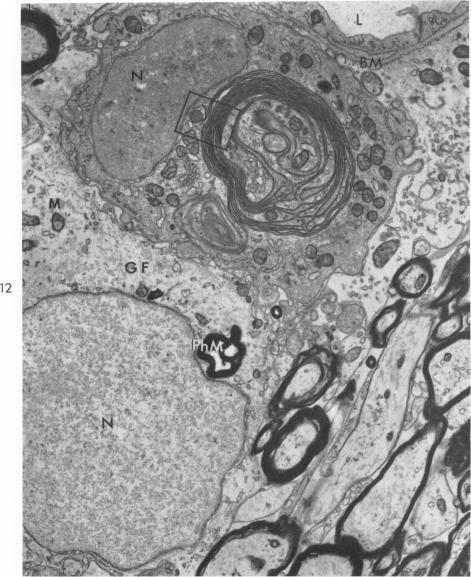

Phagocytosis and regeneration of myelin in an experimental leukoencephalopathy.

Am J Pathol. 1964 Apr;44(4):565-83.

PMID:5877506

原文链接:https://pmc.ncbi.nlm.nih.gov/articles/PMC1907034/